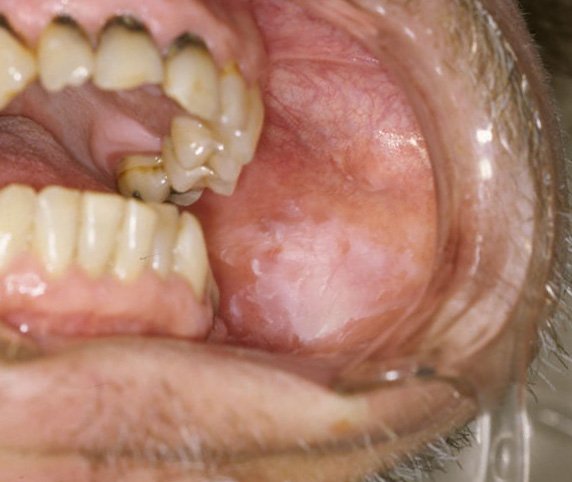

Cas Clinique 2 : Lésion Blanche de la Muqueuse Jugale et Suspicion de Leucoplasie

Patiente : Femme de 54 ans, tabagique active (25 paquets-années), consulte pour une lésion blanche de la face interne de la joue gauche, asymptomatique, découverte fortuitement. Présente depuis environ 6 mois.

Problématique identifiée : Lésion blanche non détachable au grattage, à bords bien définis, de 1,5 cm de diamètre. Le diagnostic différentiel inclut leucoplasie simple, leucoplasie verruqueuse, lichen plan, ou candidose chronique.

Prise en charge :

- Cytologie exfoliative initiale : négative pour les signes de dysplasie

- Traitement antifongique d’épreuve (fluconazole) négatif : lésion non modifiée

- Biopsie incisionnelle en zone de transition saine/lésionnelle, sous anesthésie locale

- Résultat anatomopathologique : dysplasie légère — leucoplasie à potentiel malin

Résultat : Patiente adressée en unité d’oncologie buccale pour surveillance rapprochée et sevrage tabagique accompagné.

Point clé illustré : Toute lésion blanche persistante > 2 semaines chez un fumeur doit bénéficier d’une biopsie. La cytologie seule est insuffisante pour exclure une dysplasie.